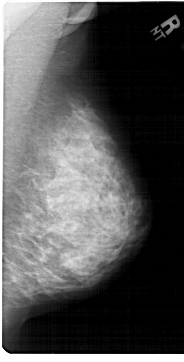

A_1453_1.RIGHT_CC

RIGHT_CC LINES 5986 PIXELS_PER_LINE 3241 BITS_PER_PIXEL 12 RESOLUTION 43.5 NON_OVERLAY